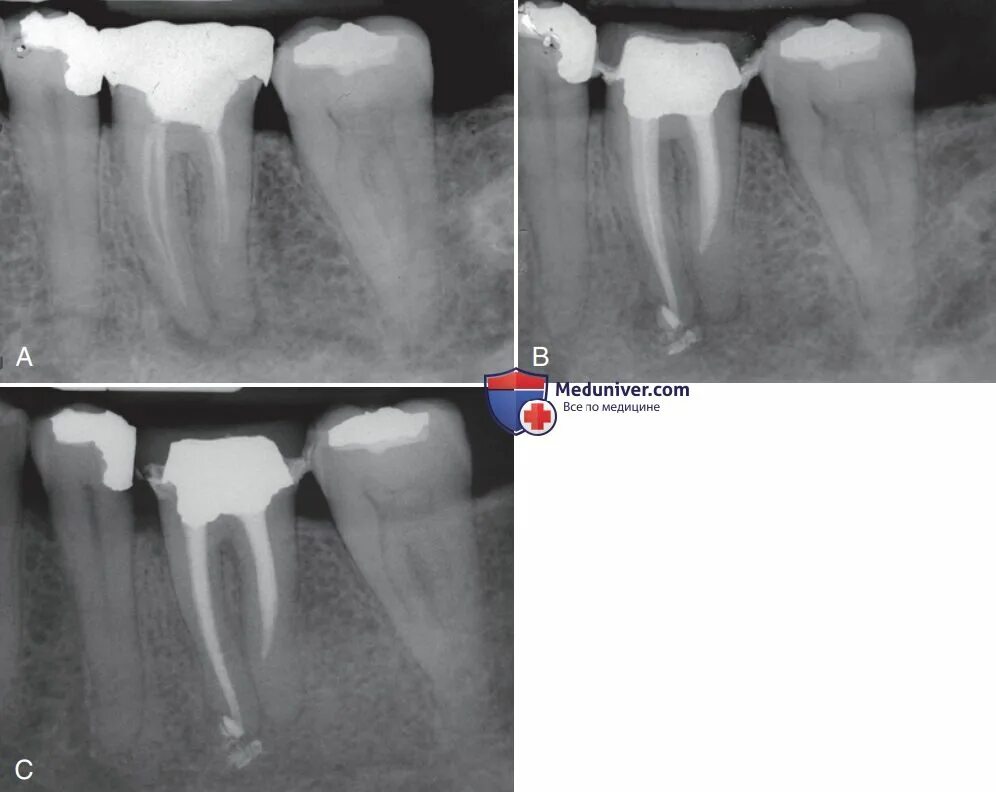

Обтурация корневого канала рентген. пульпит 17 зуба рентген с запломбированными каналами. пломбировка каналов зуба рентген.

Апикальный периодонтит рентген. периодонтит верхнего моляра рентген. снимок зуба 16 периодонтит.

Периодонтит зуба рентген. кариес пульпит периодонтит рентген. хронический апикальный периодонтит рентген.